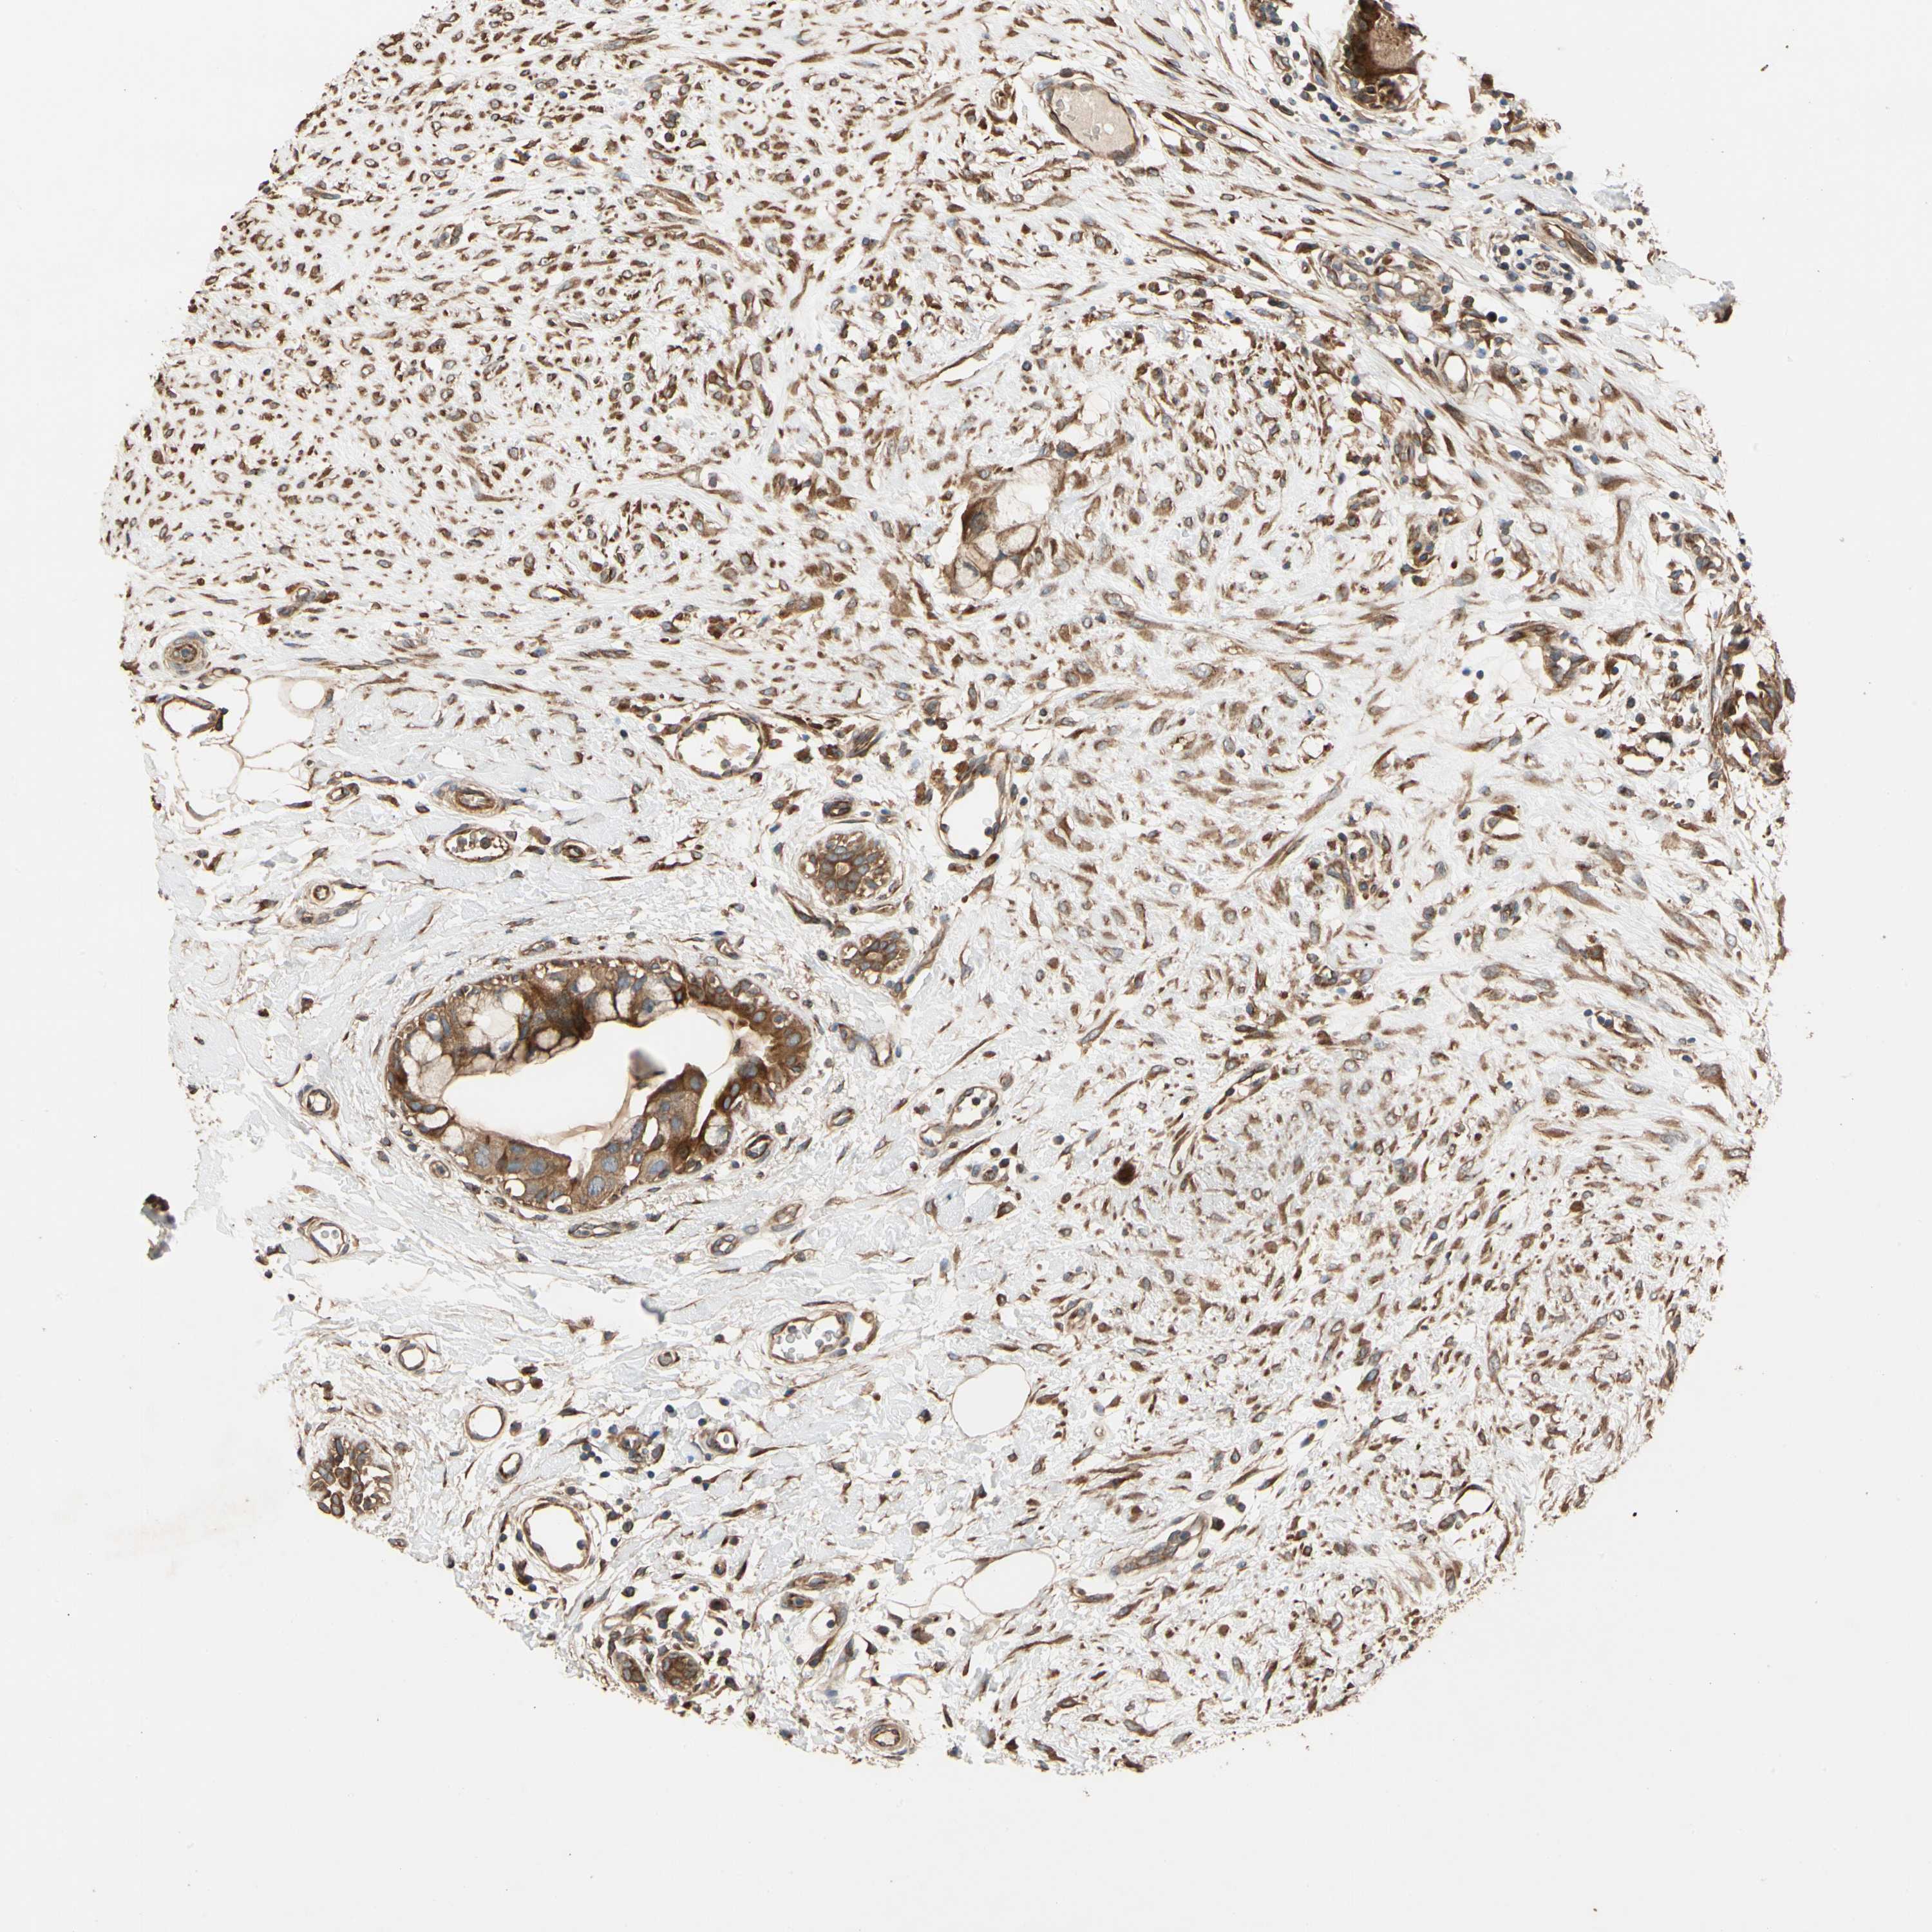

CANCER BREAST CANCER Show tissue menu

BRCA TCGA BRCA VALIDATION PROTEIN EXPRESSION